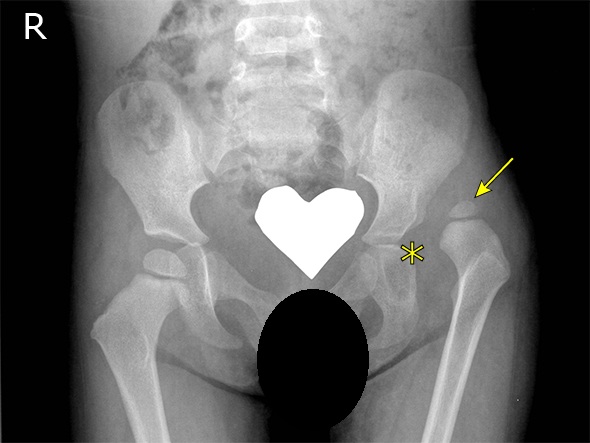

对于这个病人,第一步要做的就是到医院去拍一个骨盆的正位X线片,如下图。

假设这个图就是这名患者的骨盆正位片,是可以看到右边的股骨头半脱位的,如果存在明显的股骨头坏死或者股骨头直接塌掉了的话,X线上也可以看出来。